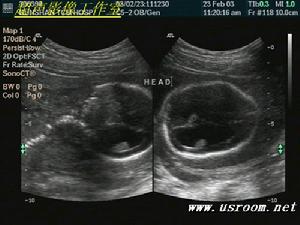

腦積水在人群中的總發病率尚不清楚,在新生兒的發生率為0.3%~0.4%。如腦積水作為嬰幼兒單一先天性病變其發生率為0.09%~0.15%;伴有脊膜膨出和脊柱裂者中其發生率為0.13%~0.29%。遺傳性導水管狹窄(女性遺傳男性發病)在先天性腦積水中不足2%。獲得性(後天性)腦積水有明確病因其發生率也因原發病而異。